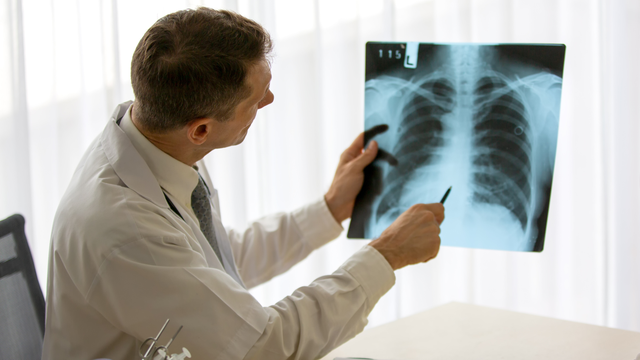

:format(webp)/chup_x_quang_xo_phoi_giai_phap_chan_doan_som_nhung_dau_hieu_bat_thuong_ve_benh_1_ec0fe169b9.png)

Xơ phổi là một tình trạng y tế nghiêm trọng, xảy ra khi mô phổi bị tổn thương và thay đổi cấu trúc dẫn đến việc mất khả năng cung cấp oxy hiệu quả cho cơ thể. Một trong những phương pháp phổ biến và hiệu quả nhất trong việc phát hiện bệnh là chụp X-quang xơ phổi. Hãy cùng Nhà Thuốc Long Châu tìm hiểu về thông tin này trong bài viết dưới đây.